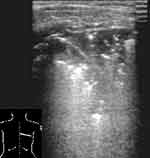

При снижении воздушности легочной ткани вследствие пневмонической инфильтрации или ателектаза, она становится эхографически видимой, имеет пониженную эхогенность и однородную эхоструктуру. Контур пневмонического очага в начале заболевания довольно ровный, форма может быть различной. В случае долевой пневмонии он повторяет форму доли, при сегментарной может иметь пирамидальную форму с основанием, обращенным к плевре, очаговой — неправильную, близкую к округлой. В безвоздушных пневмонических очагах бывают видны эхогенные, ветвящиеся, прерывистые полоски, являющиеся заполненными воздухом бронхами, а так же трубчатые анэхогенные структуры — сосуды или заполненные жидкостью бронхи и реже — тонкие линейные эхогенные полоски — соединительно-тканные межсегментарные перегородки (Рис. 2, 3). Эхогенная полоска плевры над безвоздушным участком (пневмоническим очагом или ателектазом) выглядит гораздо тоньше, чем над воздушным легким. Но это происходит не из-за «истончения плевры» [1], а из-за отсутствия составляющей отражения от поверхности воздушного легкого в комплексе плевральной эхогенной полоски. Пневмонические участки в наших наблюдениях имели несколько пониженную или среднюю эхогенность и не были гиперэхогенными, как указывают некоторые авторы [9, 2]. По мере же пневматизации при рассасывании инфильтрата в них появлялись множественные сливающиеся гиперэхогенные участки пневматизации. А высокая эхогенность при «свежих» пневмониях отмечалась за безвоздушными участками на границе с воздушной легочной тканью вследствие дистального усиления.

[Увеличить]

Рис. 2. Пневмонический очаг, содержащий эхогенные полоски воздуха в бронхах и тонкую межсегментарную перегородку.

Рис. 3. Пневмонический очаг с заполненными жидкостью бронхами.